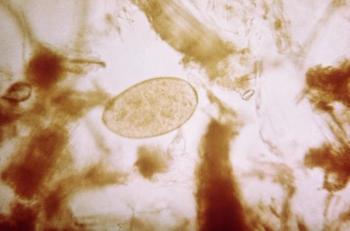

Over time, Egaten, an antiparasitic, can increase the QTc interval, resulting in a heart rhythm condition that can cause chaotic heartbeats.